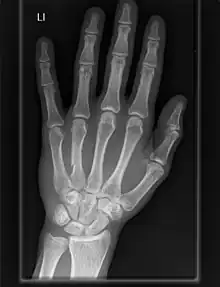

The carpometacarpal (CMC) joints are five joints in the wrist that articulate the distal row of carpal bones and the proximal bases of the five metacarpal bones.

- The second metacarpal articulates primarily with the trapezoid and secondarily with the trapezium and capitate.

- The third metacarpal articulates primarily with the capitate,

- The fourth metacarpal articulates with the capitate and hamate.

- The fifth metacarpal articulates with the hamate.

Among themselves, the four ulnar metacarpals also articulates with their neighbours at the intermetacarpal articulations.[7]